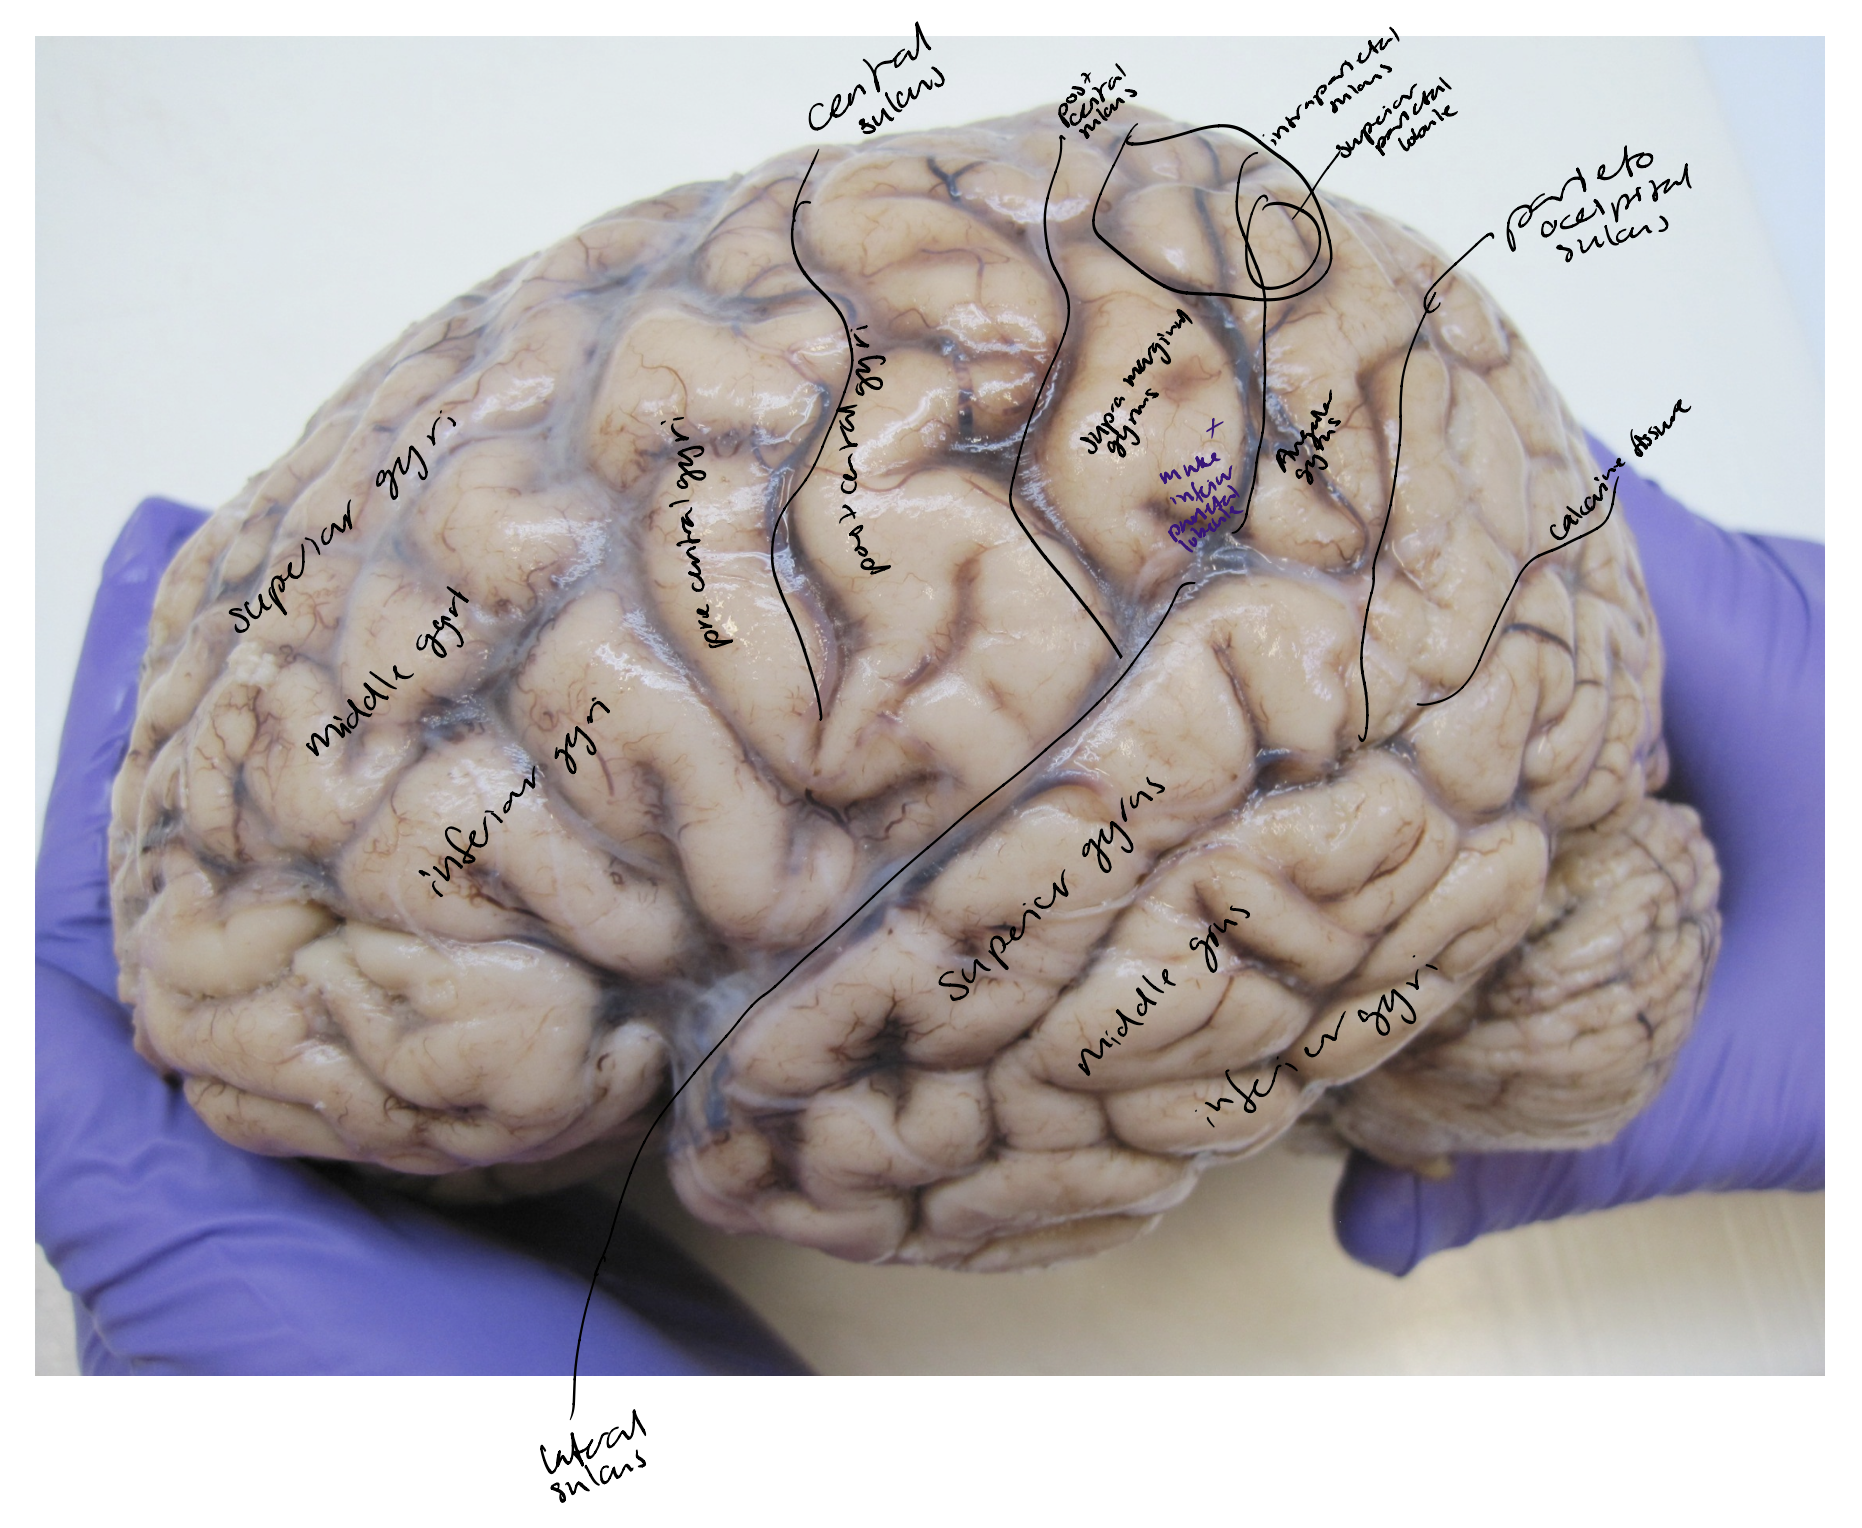

Central sulcus

The precentral and postcentral gyri

The central sulcus

Lateral sulcus

Parietooccipital sulcus

Precentral and postcentral gyri & sulci

Frontal sulci & gyri

Temporal sulci & gyri

Intraparietal sulcus

Superior parietal lobule

Supramarginal gyri

Angular gyri